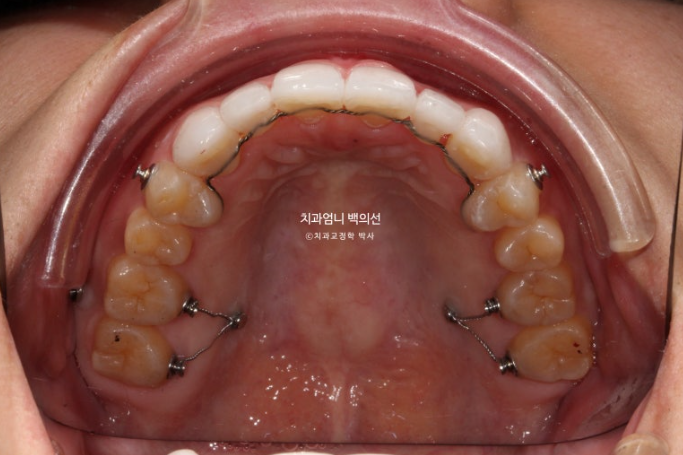

23.05~25.05

유지장치도 꼼꼼하게 들어갑니다.

개방교합 재발을 위해서는 치열을 단단하게 잡아주는 비베라가 좋습니다. 비베라 제작 권유드렸고 현재는 비베라 장치가 도착하길 기다리는 중입니다.